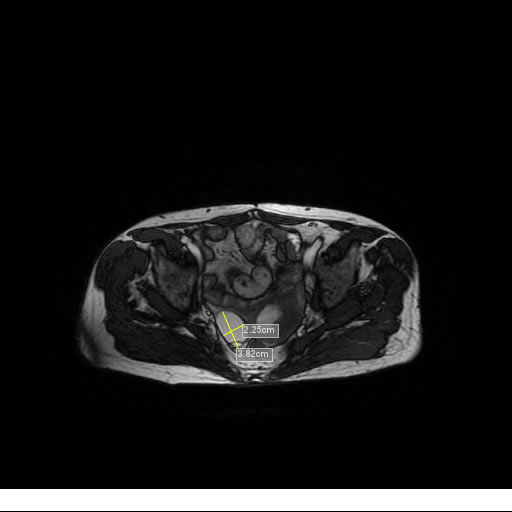

Se realizan adquisiciones en diferentes planos, con secuencias Spin echo y GRE, ponderadas a T1 y a T2, se utilizan pulsos de saturación de grasa y se administra medio de contraste a base de gadolinio.

El útero está en retroversión, retroflexión, y en posición central, se observa liquido en la cavidad endometrial, debido a la presencia de un Ca endometrial; en el anexo derecho se observa una masa quística que mide 3.8 x 2.2 cm de diámetro, corresponde a un quiste bilobulado, posee pared gruesa con componente solido puede tratarse de un Cistoadenocarcinoma, el cual realza con el medio de contraste de forma importante, entra dentro de una clasificación O-Rad tipo IV compatible con un Cistoadenocarcinoma

O-RAD tipo IV, Cistoadenocarcinoma